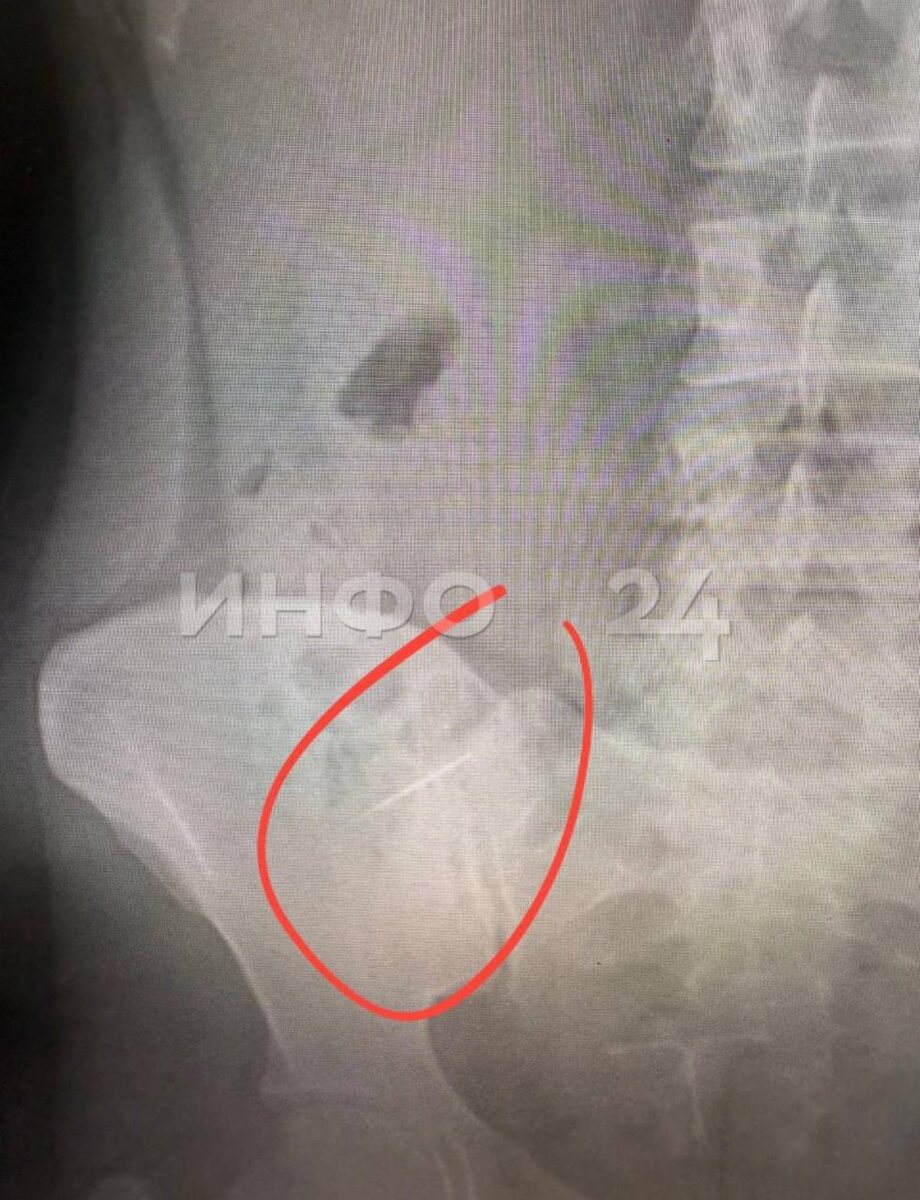

🔵🔵🔵 Стоматолог из Башкирии потерял иглу во рту пациентки. Предмет нашли в кишечнике спустя три дня.

По данным Инфо24, Екатерина поехала лечить зубы в поселок Приютово. По словам девушки, врач почему-то не использовал коффердам (латексную завесу), чтобы исключить попадание в гортань инородных тел. Доктор закончил лечение зуба, и девушка при глотании почувствовала небольшой укол. Екатерина сказала об этом врачу, но тот заявил, что, скорее всего, это был кусочек пломбы. Екатерину все же отправили на УЗИ в стоматологической клинике, там ничего не нашли.

В понедельник она поехала долечивать зуб, попросила пересчитать инструменты, врач сказал, что все на месте. Но у Екатерины начал болеть живот, новый рентген показал, что в кишечнике — игла. Ее положили в больницу. Сейчас врачи ждут, выйдет ли предмет сам или придется делать операцию.